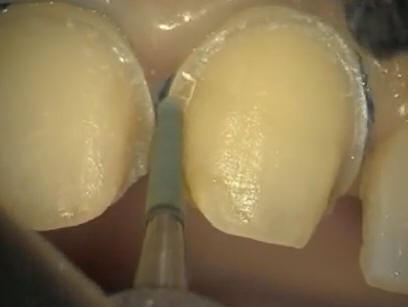

Conformación de la

corona con tiras de celuloide y pulido con discos de papael

y fresas multifilos |

Pulido con pasta

Dentbrill y brochita |

| Lavar, secar y

observar si textura se encuentra libre de poros |

Caso

terminado |